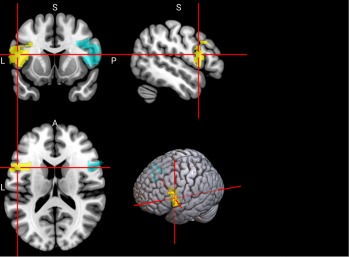

66

L & R Inferior parietal gyrus, excluding supramarginal and angular gyri (IPG)

The inferior parietal gyrus is involved in attentional, semantic, and social cognitive functioning [65].

/word/media/image14.png/word/media/image14.png